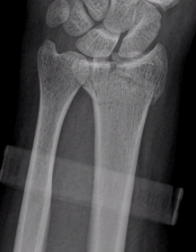

![]() |